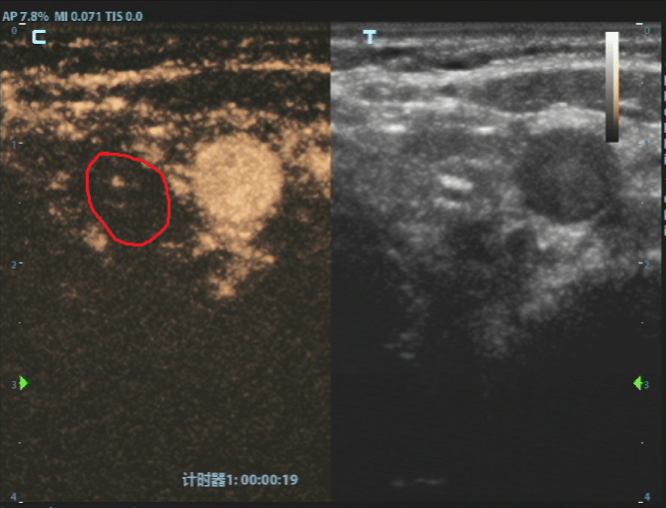

这个方案瞬间让刘女士放下了所有的担忧。随后,白国栋主任团队便为她实施了超声引导下甲状腺结节射频消融术,整个过程仅十几分钟。治疗结束时,刘女士几乎不敢相信地说,“就这么好了?我根本没有任何不舒服的感觉。”

消融后病灶

白国栋主任介绍,甲状腺微小乳头状癌通常发展缓慢,预后极好,患者不必过度恐慌。射频消融术作为一种成熟的超微创治疗手段,正是为这类符合条件的早期患者提供了更优选择,能完美满足患者“保功能、无疤痕、快恢复”的核心需求,科室已将其作为常规治疗方案,技术非常成熟。消融后的坏死组织通常在1-2年内会被身体逐渐吸收,甚至完全消失。即便未来出现新发或复发情况,仍有再次消融或手术等补救措施作为保障。